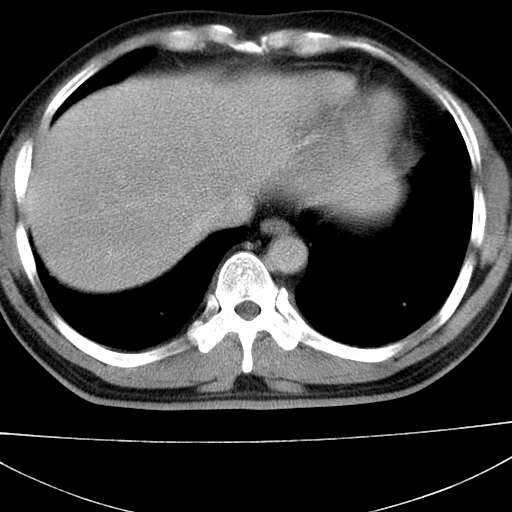

标题: CT21921:腹膜后腔肿物。患者男39Y。体检。增强扫描时间欠准

左侧膈肌脚外缘见一结节样软组织影,密度较均匀,与胸膜关系稍密切,增强轻度强化;考虑来自胸膜良性病变(胸膜纤维瘤可能)。建议加扫胸部ct检查。

左肋隔角占位,考虑胸膜间皮瘤

1)考虑左肺下叶后基底段(或左下胸后壁胸膜)软组织团块,性质待定;建议行进一步检查。2)左肾结石。

考虑左肺下叶后基底段肺隔离症?胸膜间皮瘤?

1)考虑左肺下叶后基底段软组织团块,性质待定;建议行进一步检查。2)左肾结石。

左下肺隔离症,可见从胸主动脉发出异常血管供应